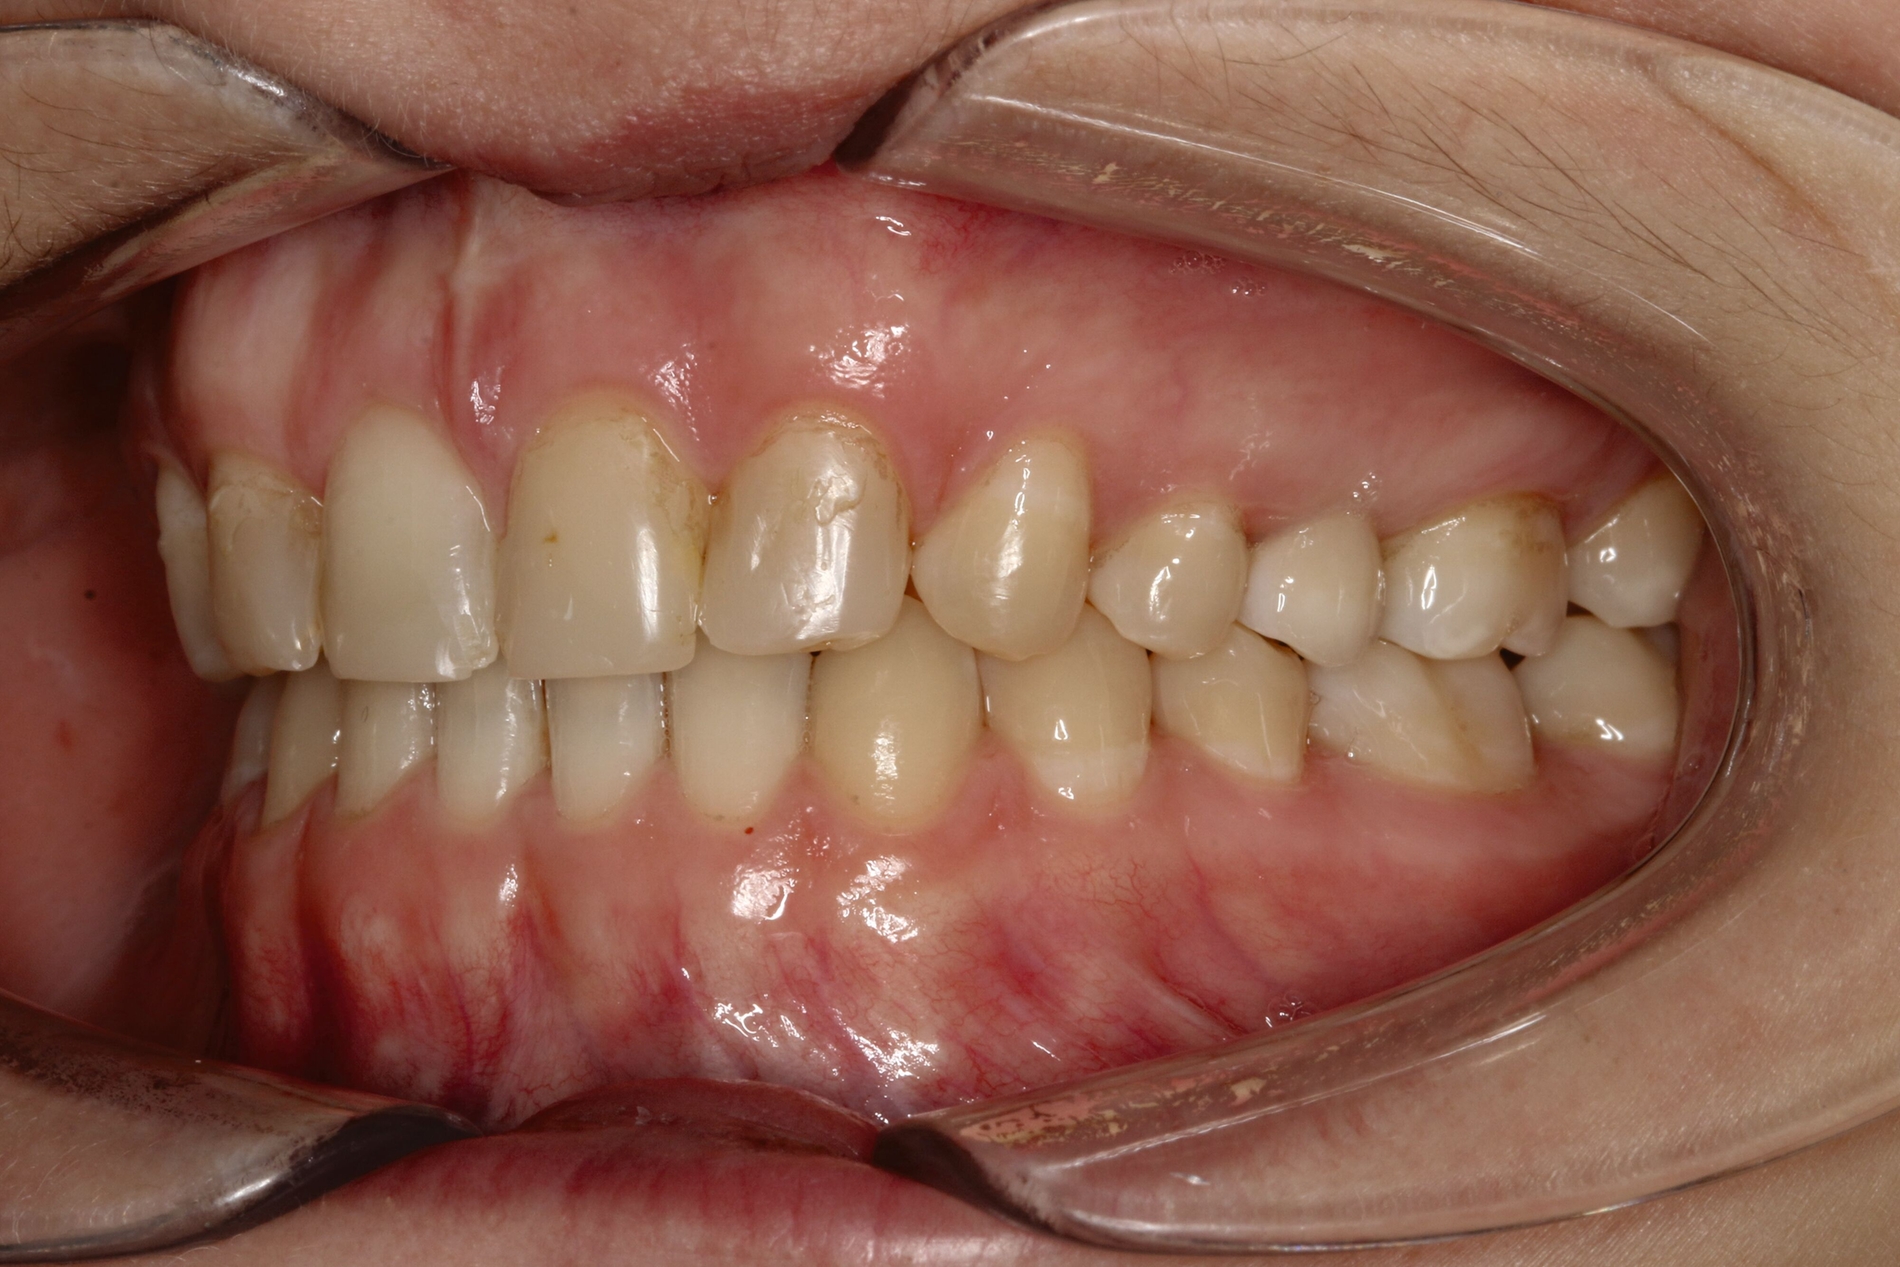

Im vorliegenden Fall stand der Zahn 23 bereits im Mesialstand bei hoher Lachlinie und tendenziell konkavem Lippenprofil. Bezüglich Morphologie und Farbe waren die Zähne 13 und 23 nicht ausgeprägt eckzahntypisch. Es bestand kein Platzmangel im Gegenkiefer. Die Patientin war bei der Erstdiagnose 12,5 Jahre alt und im Wechselgebiss der zweiten Phase mit atypischer Durchbruchreihenfolge. Es bestand eine geringfügige Klasse II. Der Overjet war vergrößert bei vertikaler Wachstumstendenz, der Overbite war um circa einen Millimeter vergrößert aufgrund der geringfügigen Steilstellung der Oberkiefer-Front. Es bestand der Verdacht auf Nichtanlage der Weisheitszähne, 15 und 25 waren verlagert.

Daher wurde ein Lückenmanagement mit Lückenschluss in der Oberkiefer-Front und Lückenöffnung mesial 16 und 26 außerhalb der ästhetischen Zone angestrebt. Eine implantatprothetische Versorgung kam aufgrund des jungen Alters der Patientin nicht infrage. Die Autotransplantation eines Prämolaren war ebenfalls ausgeschlossen, da kein Engstand und keine Indikation zur Ausgleichsextraktion bestanden.